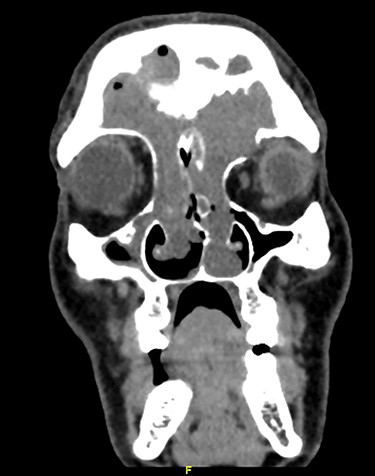

Magnetic resonance image (MRI) scanning also demonstrated a mass lesion involving both frontal and ethmoid sinuses, more into left FS causing expansion and rarefaction of the sinus wall, as well as extension of superior wall of left with extracoronal component causing mild proptosis. The lesion showed intermediate T2 signals with areas of high T2 signal along with postcontrast enhancement. No intracranial extension noticed (Figs 2 and 3).

Coronal MRI of paranasal sinuses, T1-weighted image post contrast.